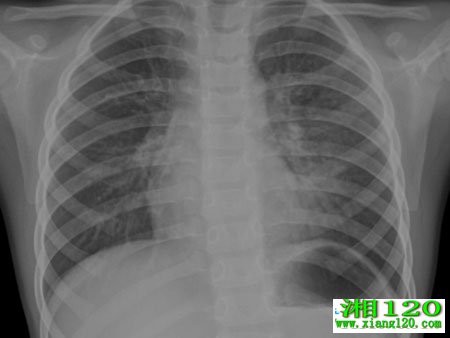

肺炎的病因有很多,大部分人都公认的原因是吸烟。吸烟对肺功能的影响很大,并不仅仅是引发肺炎也会导致更加严重的恶性疾病的发生。据研究发现,吸烟者比比吸烟者患的几率高10倍,吸烟家庭的孩子比不吸烟的家庭孩子患的几率高2倍,戒烟势在必行。